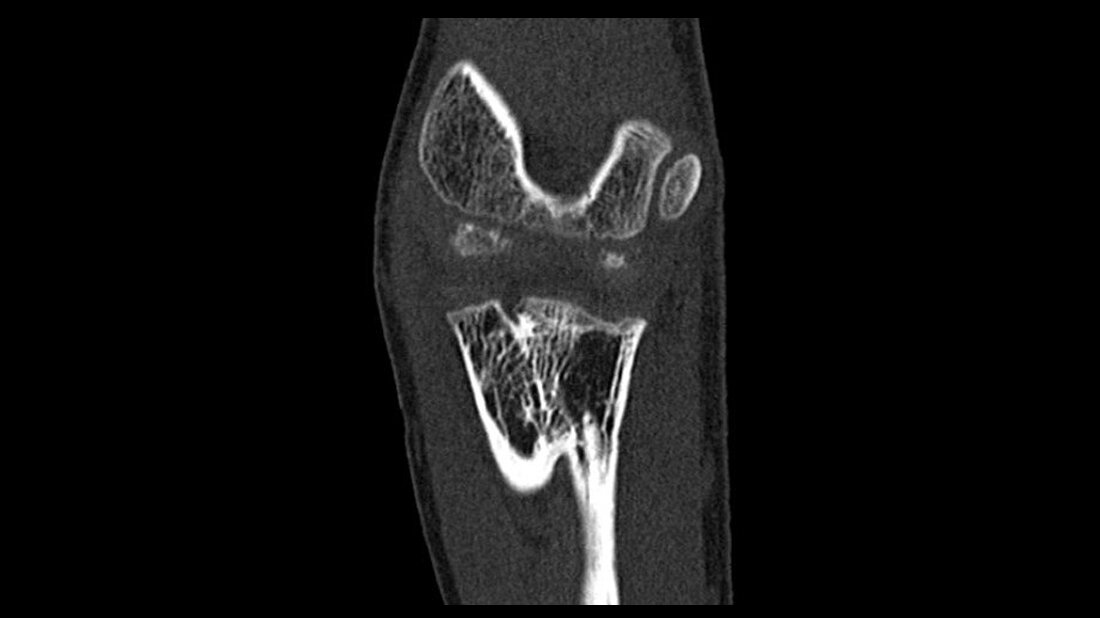

Die radioulnare Synostose verursacht eine Einschränkung der aktiven und passiven Rotationsbewegung des Unterarms. Patienten mit einer kongenitalen proximalen radioulnaren Synostose kommen nicht so häufig vor. Sie haben eine auffällige Beugedeformierung des Radius und eine interne Rotationsdeformität von Radius und Ulna.

Radioulnar synostosis is a bony connection between radius and ulna, which causes restriction of the active and passive rotational movement of the forearm. Patients with congenital proximal radioulnar synostosis are not so often. They have remarkable flexion deformities of the radius and internal rotation deformity of the radius and ulna.